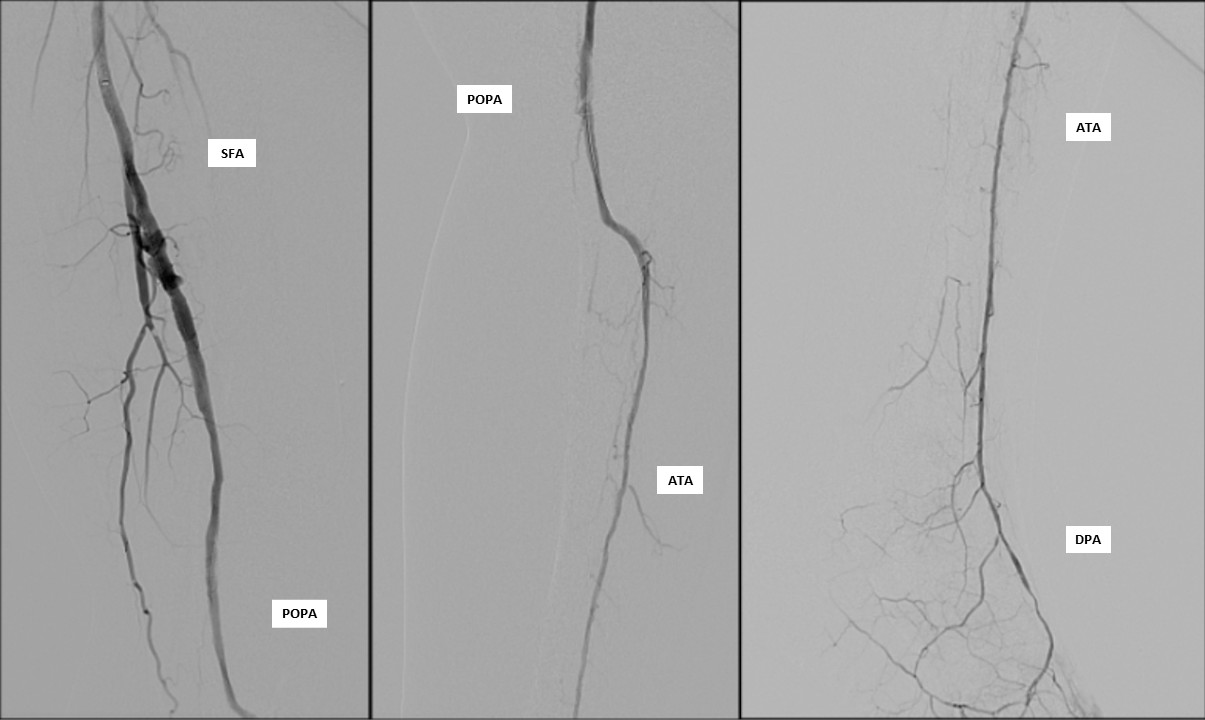

Doppler ultrasound demonstrated triphasic waveform at the left common femoral artery and biphasic flow at the mid superficial femoral artery (SFA). There was total occlusion from the distal SFA to the distal popliteal artery, with monophasic high end-diastolic flow at the anterior tibial artery (ATA), consistent with severe infra-popliteal ischemia.

Diagnostic arteriography showed total occlusion of the distal SFA with poor distal runoff. Reconstitution was identified only at the distal ATA as the single suitable target vessel.

Antegrade puncture was performed, and a microcatheter with a Command 14 guidewire (Abbott Vascular, Santa Clara, CA, USA) was advanced toward the distal SFA but failed to cross because the proximal cap was misidentified due to its blunt and ambiguous appearance. The wire entered aside branch that ran parallel to the true SFA–popliteal course. Given the long chronic total occlusion (CTO) segment and uncertain vessel path, a retrograde approach was pursued to overcome this anatomical ambiguity. Distal ATA access was gained and a CXI Support Catheter (Cook Medical, Bloomington, IN, USA) with a V-18 Guidewire (Boston Scientific, Marlborough, MA, USA) was advanced retrogradely into the popliteal artery but failed to meet the antegrade wire. Another retrograde access from popliteal artery followed a consistent tract. Further attempt from the ATA successfully approached the proximal cap. A 4.0 ¡¿80 mm balloon was advanced retrogradely and inflated at 10 atm. From the antegrade route, the BeBack Crossing Catheter (Bentley InnoMed, Hechingen, Germany) was aimed toward the inflated balloon and successfully punctured the proximal cap, entering the balloon and confirming re-entry. Lesion preparation was completed antegradely, followed by drug-eluting stent deployment in the SFA, drug-coated balloon angioplasty of the popliteal–proximal ATA segment, and plain old balloon angioplasty of the distal ATA to DPA. Final angiography demonstrated excellent in-line flow to the plantar arch.